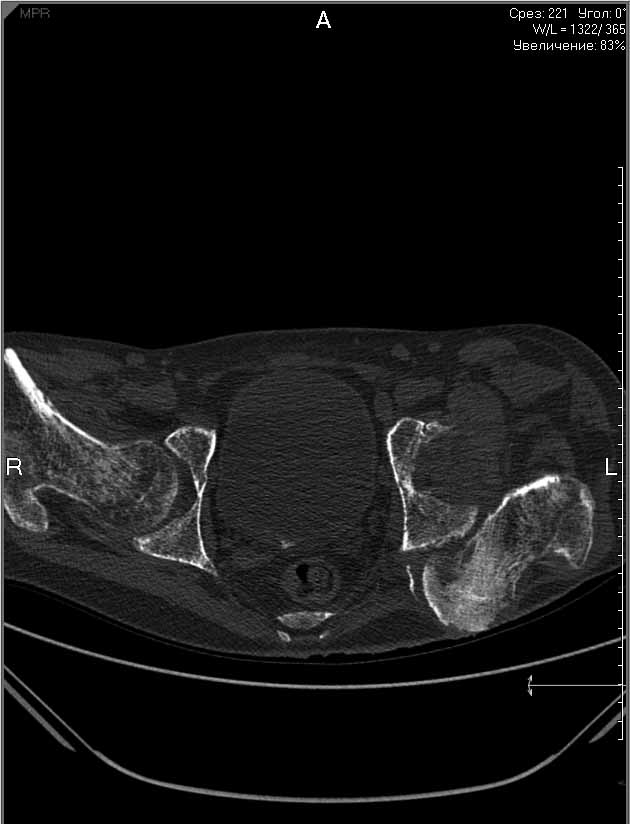

Пациенту 22 года. Травма в июле 2010г, лечился в районной больнице. К нам попал в апреле 2011г.Тяжелая сочетанная травма (29.07.2010): тупая травма живота с повреждением внутренних органов. Закрытая травма грудной клетки с переломом ребер. Пневмоторакс справа. Тяжёлая позвоночно-спинномозговая травма. Закрытый осложнённый переломо-вывих С5 позвонка. Верхний парапарез, нижняя параплегия, нарушение функции тазовых органов по типу недержания. Цекостома. Пролежень левой ягодичной области. Неправильно консолидированные переломы верхних третей обеих бедер. Застарелый вывих левого бедра.Осложнение: Поддиафрагамльный абсесс слева, забрюшинного пространства. Свищ желудка и ободочной кишки. Синегнойный сепсис. Двухстороняя пневмония. Но это уже анамнез.Пациент был неоднократно оперирован на органах брюшной полости и осложнениями с ними связанными.

В ягодичной области слева глубокий пролежень размером 2х2см, дном является вывихнутая головка бедра. Неврологически в нижних конечностях динамика положительная, появились движения в правой стопе, чувствительность в стопах.По переломам бедер: подвижности в местах переломов нет, снимки высылаю.